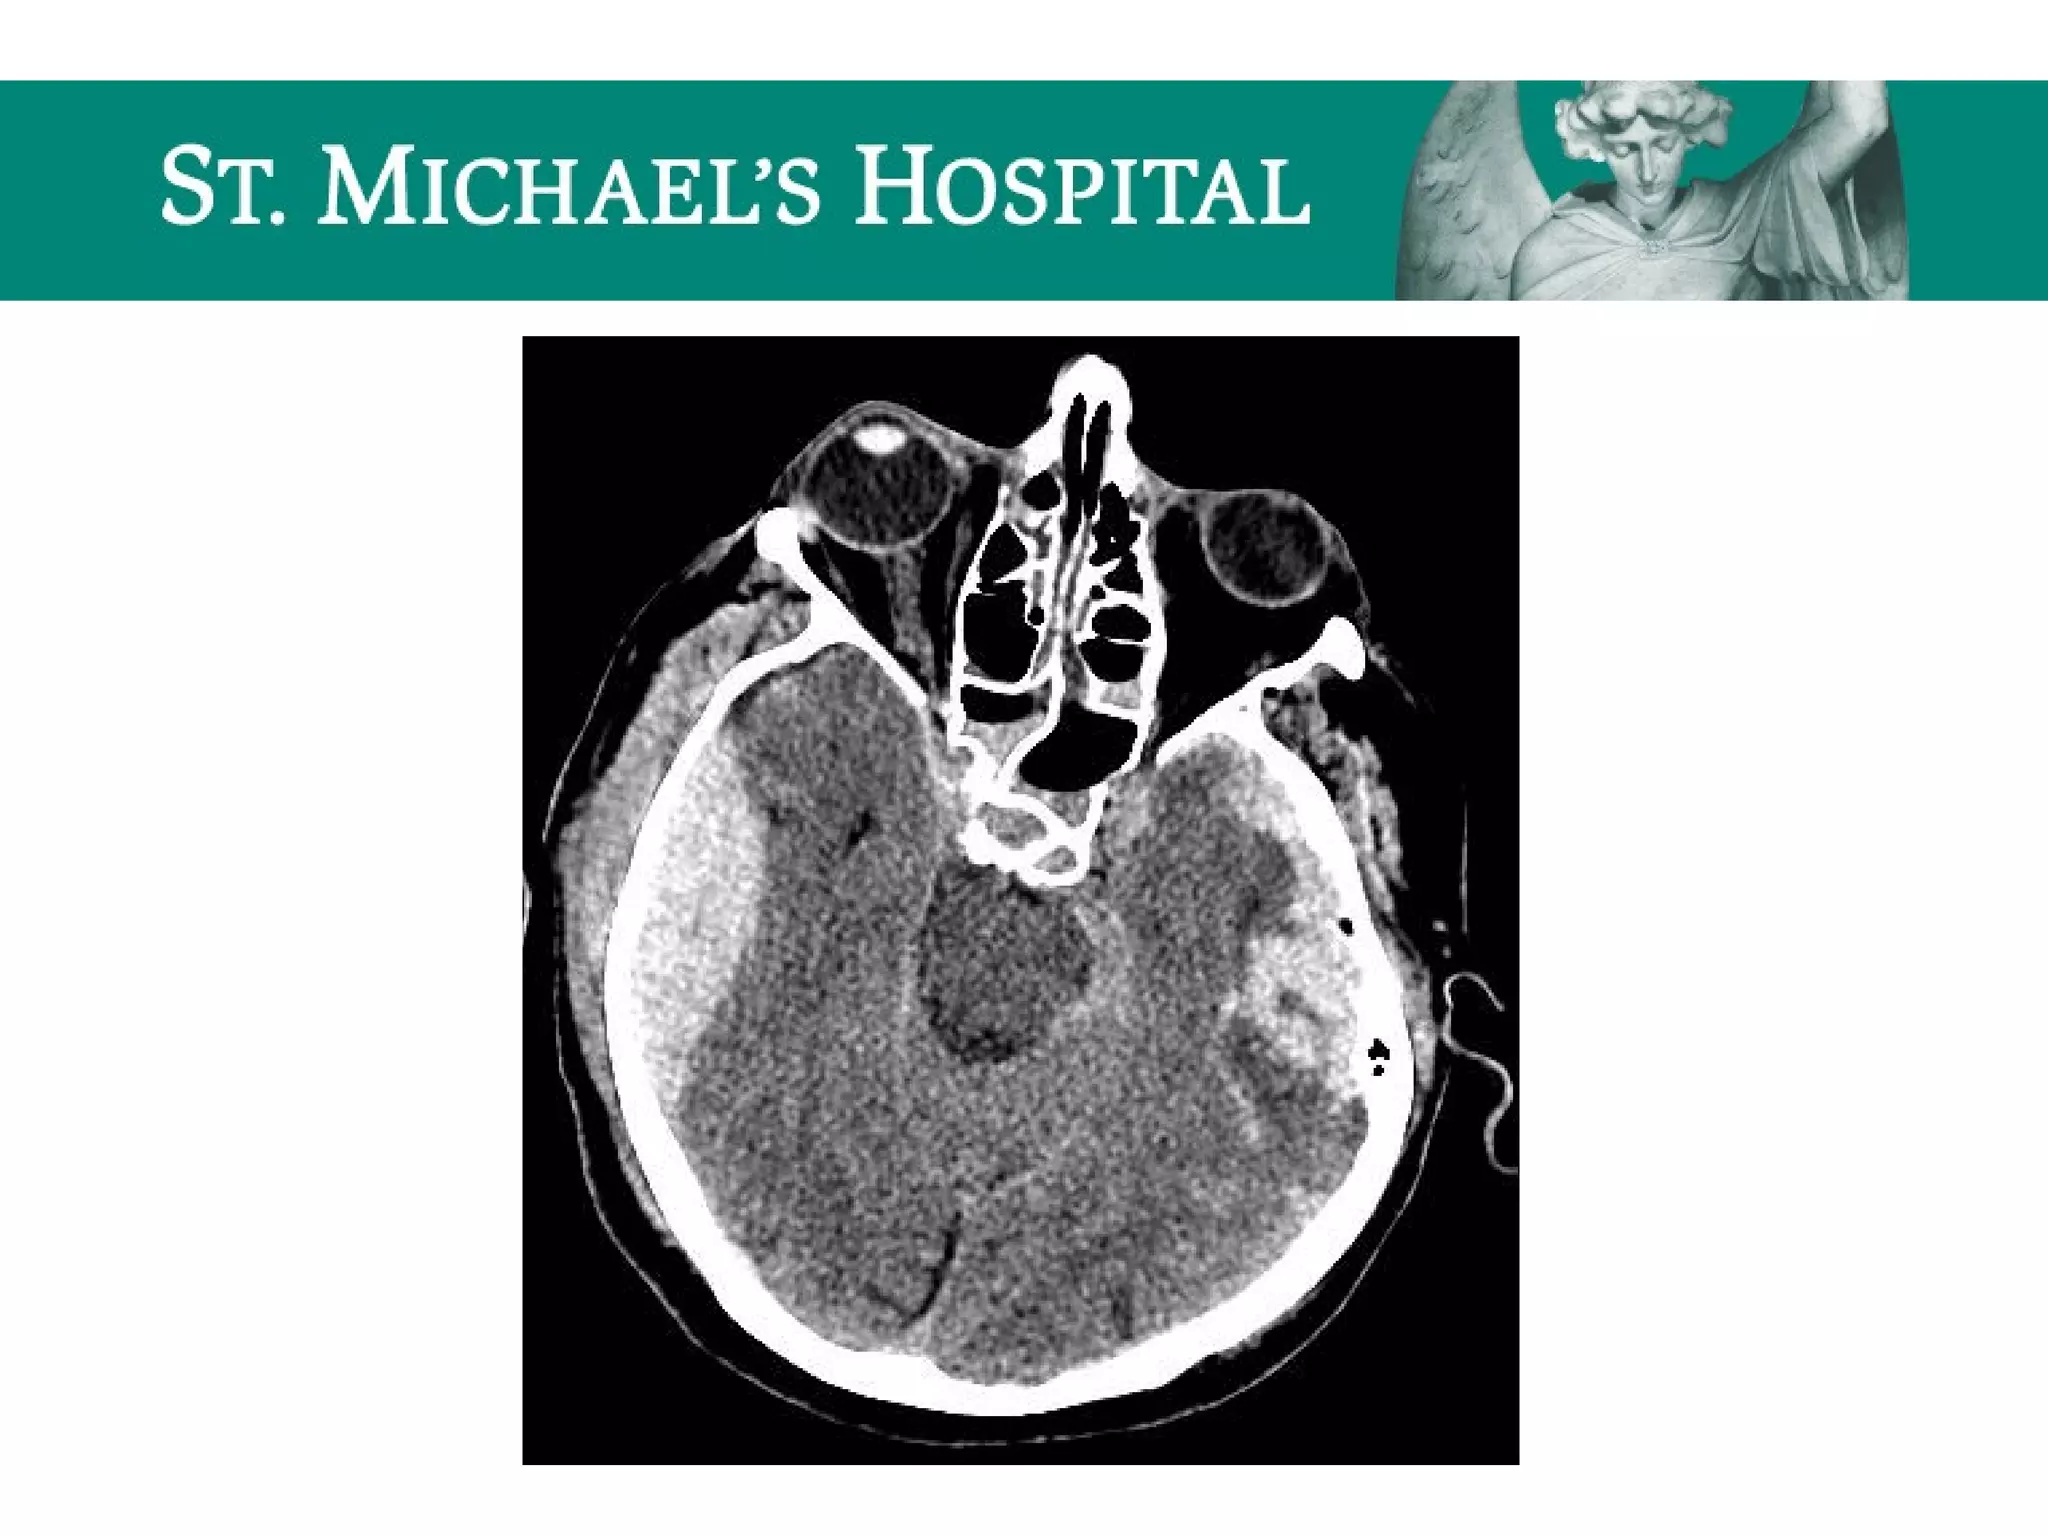

Global Cerebral Ischemia/Anoxic Brain

Injury

 Diffuse brain swelling/edema can result in:

 global loss of gray-white differentiation

 global sulcal/cisternal effacement

 pseudo-subarachnoid hemorrhage

 dense cerebellum

Global Cerebral Ischemia/AnoxicBrain Injury  Diffuse brain swelling/edema can result in:  global loss of gray-white differentiation  global sulcal/cisternal effacement  pseudo-subarachnoid hemorrhage  dense cerebellum